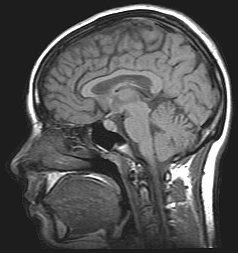

![]() Corte sagital en una imagen por resonancia magnética. | ||

Los planos sagitales son en anatomía aquellos planos, perpendiculares al suelo y en ángulo recto con los planos frontales, que dividen al cuerpo en mitades (izquierda y derecha). El término anatómico sagital fue acuñado por Gerardo de Cremona.[1]

El plano mediano (llamado también plano sagital y medio, mediosagital, medial o medio, T.A. (Terminología Anatómica): planum medianum) es un plano sagital especial que, siendo perpendicular al suelo, pasa exactamente por la mitad del cuerpo, dividiéndolo en dos partes iguales, derecha e izquierda.